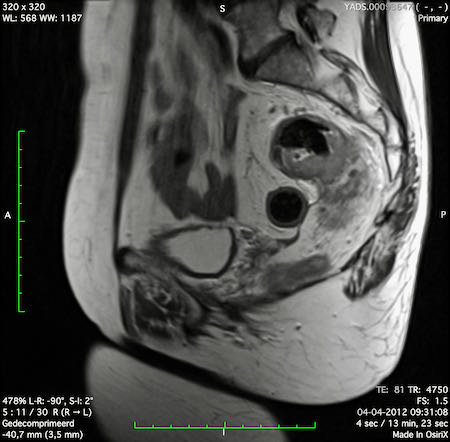

Hình ảnh

Các hình ảnh được cung cấp cho thấy ung thư biểu mô tế bào nhẫn với tình trạng dày lan tỏa thành trực tràng, hình ảnh bia bắn điển hình, và sự xâm lấn mỡ mạc treo trực tràng.